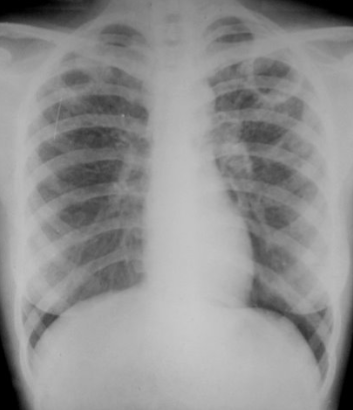

Rx toracică, incidență P-A

DESCRIERE:

DX: emfizem pulmonar

DD: